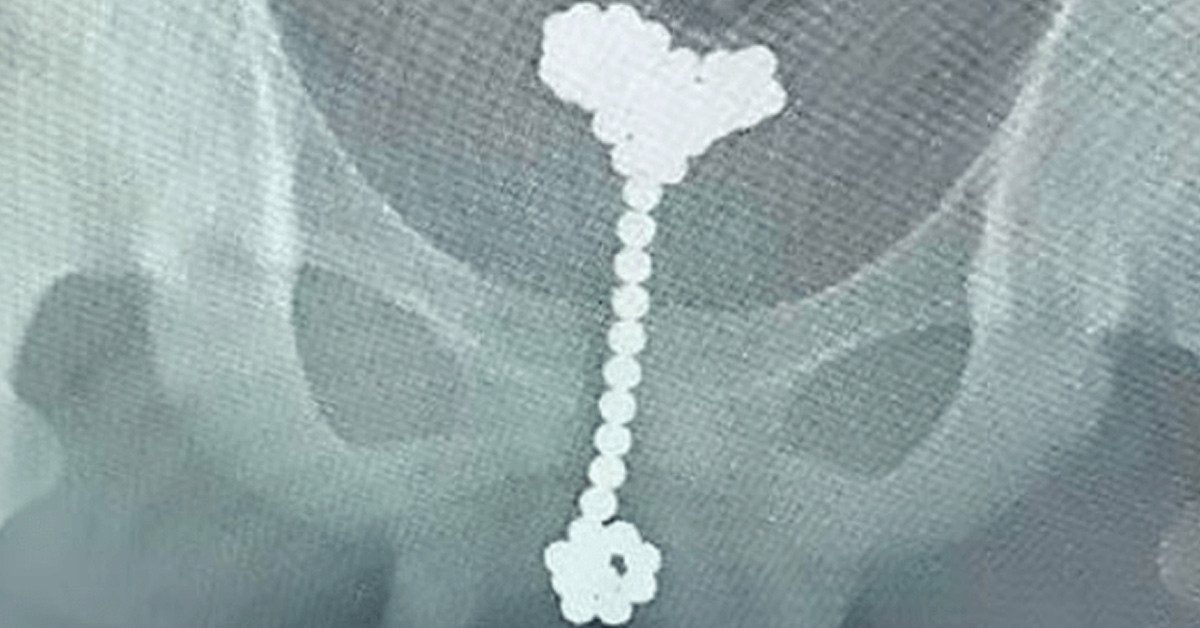

Röntgen çekilen Hua'nın içinde yer alan 53 topun iki sütuna hizalanan posterior üretra bölgesinde sıkışıp kaldığı ortaya çıktı. Ameliyat alınan Hua'nın erkeklik organından 53 tane top çıkarıldı ve 14 yaşındaki çocuk eski sağlığına kavuştu. 14 yaşındaki Jiang Hua'nın erkeklik organına 53 tane manyetik top sokması Çin medyasında da büyük ses getirdi.